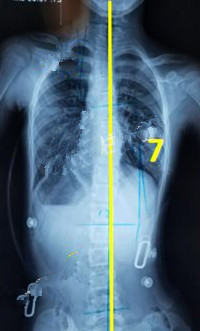

脊柱側(cè)彎矯形器(支具)是通過外力對側(cè)彎的脊柱進(jìn)行矯正。所以,支具的力點位置及大小非常重要。當(dāng)患者生長發(fā)育速度較快或支具矯正效果較好時,側(cè)彎矯正的進(jìn)程也會較快,此時為了充分利用孩子生長階段的最佳矯正期,一定要對支具進(jìn)行及時的調(diào)整和更換。

一般經(jīng)過三個月至六個月的治療,對稱度都能得到改善,力線回正。

此時由于患者已經(jīng)完全適應(yīng)支具的力點,且體表變化較大,為了進(jìn)一步矯正,我們需要對支具進(jìn)行調(diào)整。如果由于孩子身高的變化較大,為了更進(jìn)一步的矯正,可以考慮更換新的支具。

未穿支具